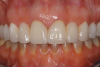

A patient presented with two defective 3-unit fixed partial dentures spanning teeth Nos. 6 through 8 and teeth Nos. 9 through 11 (Figure 7). The defective fixed partial dentures were removed (Figure 8), an impression was made, and traditional provisional fixed partial dentures without ovate pontics were placed. After the impression was sent to the laboratory, the lab technician prepared ovate pontic sites on the stone cast (Figure 9) and fabricated the new definitive bridges. On the day of insertion, the provisional fixed partial dentures were removed (Figure 10), ovate pontic sites were prepared using a teardrop-shaped diamond bur (Figure 11), and the sites were sounded to confirm that there was at least 2 mm from the base of the pontic site to the alveolar bone (Figure 12). The fixed partial dentures were cemented, and the postoperative healing was uneventful (Figure 13).

(13.) Close-up retracted 2-month postoperative view of the final fixed partial dentures spanning teeth Nos. 6 through 8 and teeth Nos. 9 through 11, along with replacement crowns for the other restored maxillary teeth.

Figure 13